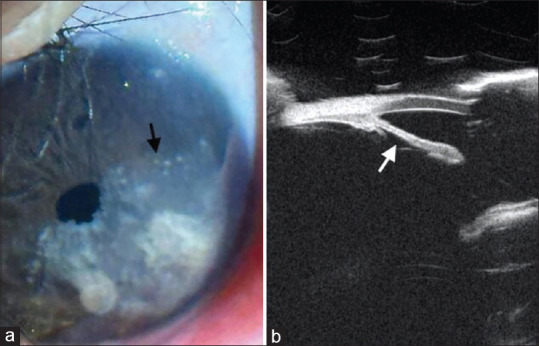

An infant with unusual iris lesions: Insights from a steroid response.

一名患有不寻常虹膜病变的婴儿:来自类固醇反应的见解。